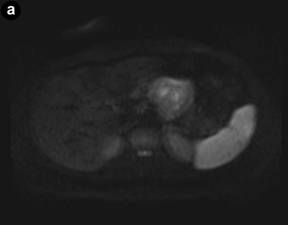

DW-MRI (Figure 4a) was performed (using b values of 50, 400 and 800) and the mean apparent diffusion coefficient (ADC) map was calculated (Figure 4b). The lesion presented a relatively high ADC value (1.8 x10-3 mm2/sec) compared to the ADC of the normal pancreatic gland (1.4 x10-3 mm2/sec), although there were some intralesional small areas of relatively low signal (minimum values of 1.3 x10-3 mm2/sec). T2/DW fusion imaging was performed (Figure 4c). Gadolinium-enhanced MR imaging (Figure 5) showed early peripheral enhancement of the fibrous pseudocapsule. No central contrast enhancement was observed.

Figure 4. a. Axial diffusion-weighted image (b value of 800 sec/mm2) shows a lesion with low signal intensity with some small central areas of higher signal intensity from restricted diffusion. b. Apparent diffusion coefficient mean value of the lesion is 1.8x10-3 mm2/sec with the central hypointense areas having a minimum value of 1.3x10-3 mm2/sec (arrows). c. T2-weighted and diffusion-weighted imaging were fused displaying a colored map of abnormal diffusion parameters. |